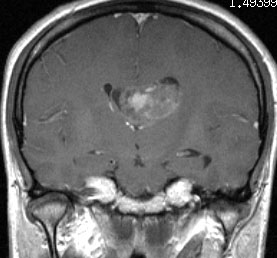

無症状の若い女性に偶然発見された例

central neurocytomaは腫瘍実質部分が多いものです。しかし,この例のように腫瘍の大部分をのう胞が占める症例もあります。

anterior transcallosal apprroachで亜全摘出しました。20代の女性でしたが,その後,子どもも生まれて元気です。

腫瘍の位置から,透明中核が発生母地であることが推測されます。central neurocytomaは,惻脳室壁にべとべとくっつくので,脳質上衣からの剥離は簡単ではありません。鑑別しなければならないのが,成人の毛様細胞性星細胞腫ですが,この症例では決定的な鑑別点はないでしょう。のう胞性の毛様細胞性星細胞腫と同様に,腫瘍の増殖力は低く無理して全摘出するものではありません。